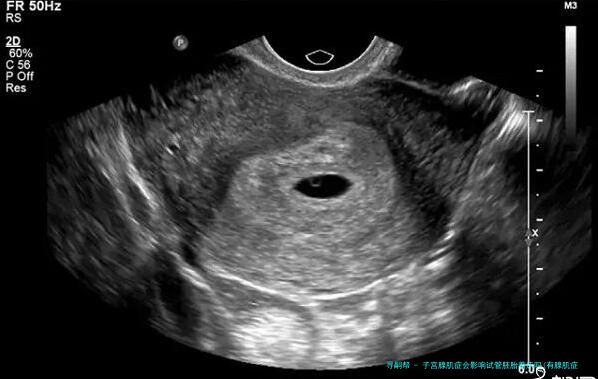

子宫腺肌症会影响试管胚胎着床吗(有腺肌症能不能做试管)

二、子宫腺肌症会影响试管胚胎着床吗?

子宫腺肌病会导致试管婴儿的成功率下降,因为在子宫腺肌病的影响下,子宫内膜会移位,引发炎症反应,子宫变大,强化了子宫的收缩功能,因而会影响胚胎的着床。很多条件下,即使胚胎植入成功,后期流产率也会高于正常人。因而想做试管婴儿的性朋友可以先做相关治疗,再做试管婴儿,以免影响试管婴儿的成功率。

子宫腺肌病一朝产生,可能会出现月经错乱、痛经等症状。这主要是因为子宫腺器官和间质侵入子宫肌层形成弥漫性或限制性病变,导致全子宫血液流动不畅,即供血不足,使子宫内膜容受性变差,从而影响胚泡的顺当着床或早产(普通子宫腺肌病多发生于30~50岁左右的产后一个月妇,但也多见于年轻未育妇或妊娠次数过多,容易发生,另有)

子宫腺肌病可以表现为1个坚硬的结节。子宫腺肌病较重的情况会像个球,导致子宫增大,质地松垮,活动本领差。统计表现,百分之十五~40%的子宫腺肌病会并发子宫内膜异位症,约对折患者会并发子宫肌瘤。因此要是不经处置直接移植胚胎,会影响胚胎的着床,降低性的怀孕率。因而关于患了子宫腺肌病的性,建议先进行试管婴儿的诊断和治疗,痊愈后再进行移植,如此成功率更高,好孕率更有保证。大家周知,子宫内膜是胚胎最终着床发生育之处,是保证着床成功率的基础。而且子宫腺肌病会直接影响子宫内膜的质量和宫内环境,所以自然会妨碍胚胎着床。